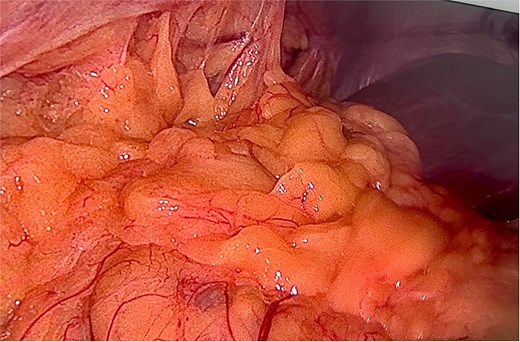

A right diaphragmatic hernia secondary to blunt abdominal trauma was diagnosed. The patient underwent laparoscopic right diaphragmatic hernia repair with mesh hernioplasty. Intraoperatively, a large defect in the right hemidiaphragm allowed omentum and hepatic flexure herniation with dense adhesions (Fig. 3). Due to the chronicity and size of the defect, complete primary closure was not feasible (Fig. 4). The defect was subsequently reinforced with a 20 × 15 cm intraperitoneal composite mesh fixed with tackers to ensure robust repair (Fig. 5). The surgical intervention was successful. The patient was discharged on Day 3, and a 5-month follow-up CT confirmed correct mesh positioning without complications (Fig. 6).

Intraoperative image reveals a right hemidiaphragm defect with omental protrusion and hepatic colon adhesion.